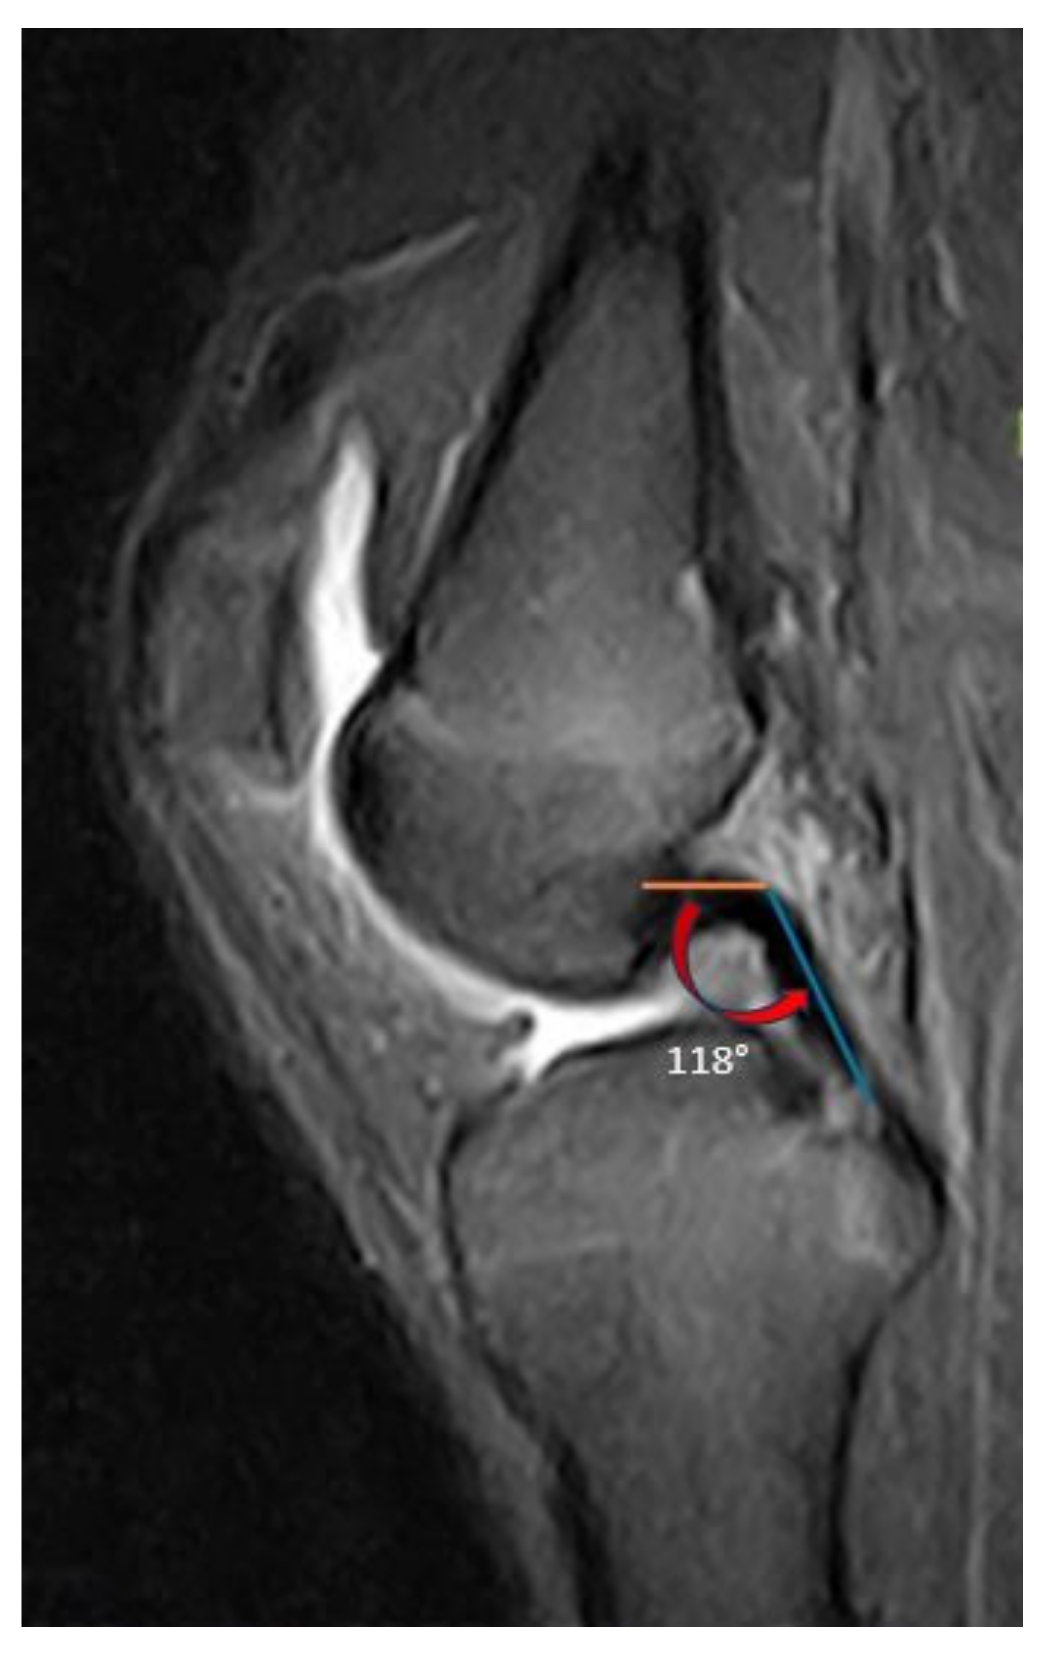

| PCL buckling angle | 125 ± 12.9 (97–154) |

| PCL buckling angle | 125.7 ± 12.4 (97–154) | 123.8 ± 13.8 (97.5–144) | 0.495 | −3.601 to 7.401 | 2.771 |